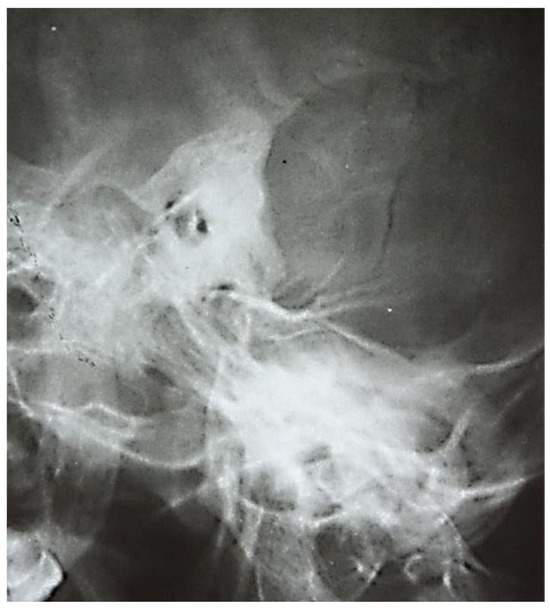

3.1.1. Conventional Radiology